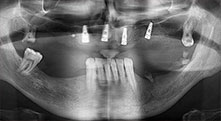

Implants

Les quatre implants sont in situ, comme prévu. Les molaires maxillaires distales peuvent toujours être utilisées pour fixer la prothèse avec revêtement qui a été introduite un mois après la pose de l'implant.